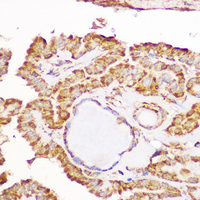

Immunohistochemical analysis of GFRA1 staining in human thyroid cancer formalin fixed paraffin embedded tissue section. The section was pre-treated using heat mediated antigen retrieval with sodium citrate buffer (pH 6.0). The section was then incubated with the antibody at room temperature and detected using an HRP conjugated compact polymer system. DAB was used as the chromogen. The section was then counterstained with haematoxylin and mounted with DPX. -